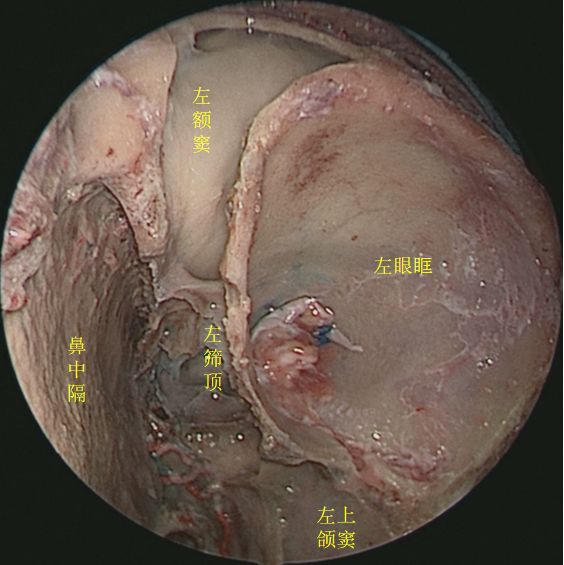

去除左侧筛窦,向上方观察筛顶 ↓

↑ 去除鼻中隔、左侧鼻腔侧壁结构及左眶内容物,前方观察各副鼻窦位置毗邻

去除左侧筛窦、左眶内容物,开放左侧额窦,观察额窦开口

开放左侧额窦前壁,观察额窦腔